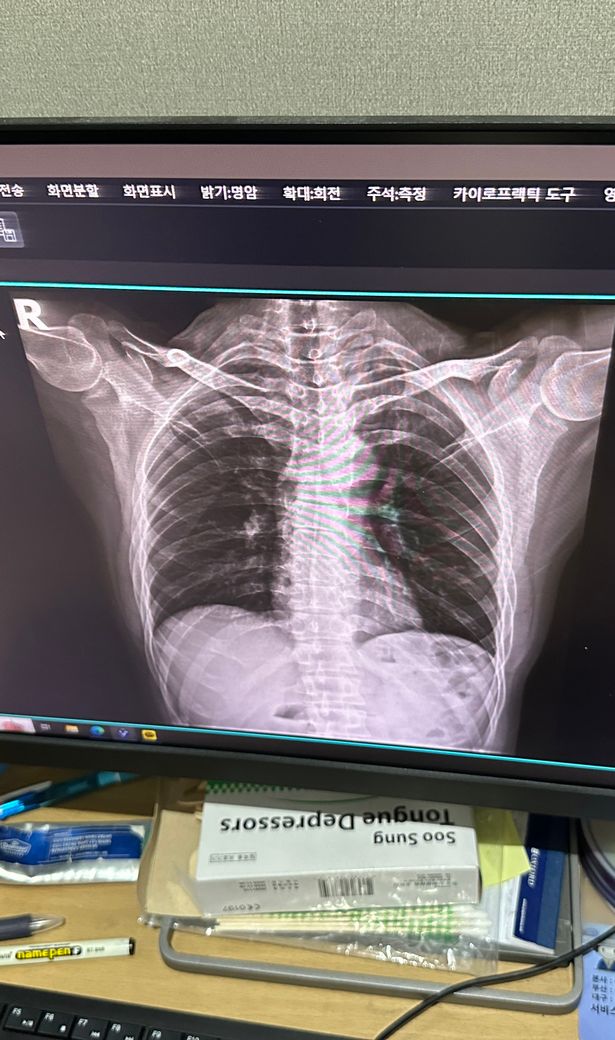

사진은 증상 생기기 일주일정도 전에 정형외과에서 찍은 사진입니다

• 2번 째 사진

엑스레이 사진을 다각도로 봐야겠지만 이 사진으로만 보기에는 흉추측만증이 있으신것 같네요 그로인해 옆구리 통증이 올수 있습니다